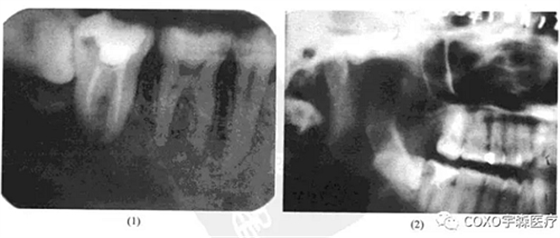

檢查:54]頰側(cè)骨膨隆,頰側(cè)活檢切口無膿性分泌,54]無松動,無叩痛,6]殘冠、x線片示:654]]冠部均有充填物,4]牙槽骨吸收已近根尖,51]牙槽骨吸收至根長1/2。全景片示:54]根尖陰影,無明顯骨質(zhì)反應(yīng)線(圖13-3),54]電活力測試無反應(yīng)。

局麻下拔除654],見根尖部有大量肉芽組織予以刮除,術(shù)后傷口順利愈合。病理報告:右下后牙區(qū)根尖周囊腫,伴反應(yīng)性骨質(zhì)增生。

本病例的臨床診斷為根尖周囊腫,似無太大疑問,但X線表現(xiàn)則十分不典型:54]根尖骨質(zhì)呈不規(guī)則、潛穴性吸收,底部幾達(dá)顏孔,更無明顯骨質(zhì)反應(yīng)線。由于54]無明顯松動及叩痛,加之頰側(cè)骨質(zhì)膨脹,致使牙體牙髓病醫(yī)師疑為腫瘤,不敢進(jìn)行根管治療術(shù)。手術(shù)結(jié)果證實仍為根尖周囊腫伴反應(yīng)性骨質(zhì)增生。結(jié)合術(shù)中見病灶區(qū)有大量肉芽組織,說明本病例的炎癥過程可能持續(xù)時間較長,程度較重,致使 線片表現(xiàn)呈不典型性。本例的經(jīng)驗是:應(yīng)牢記根尖周囊腫還有不典型表現(xiàn)者,臨床應(yīng)綜合各方面的因素考慮,方能更進(jìn)一步提高臨床診斷水平。